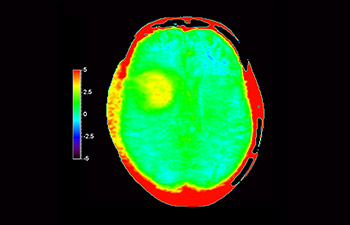

Glioblastoma recurrence

Brain imaging for glioblastoma recurrence

with 3D APT